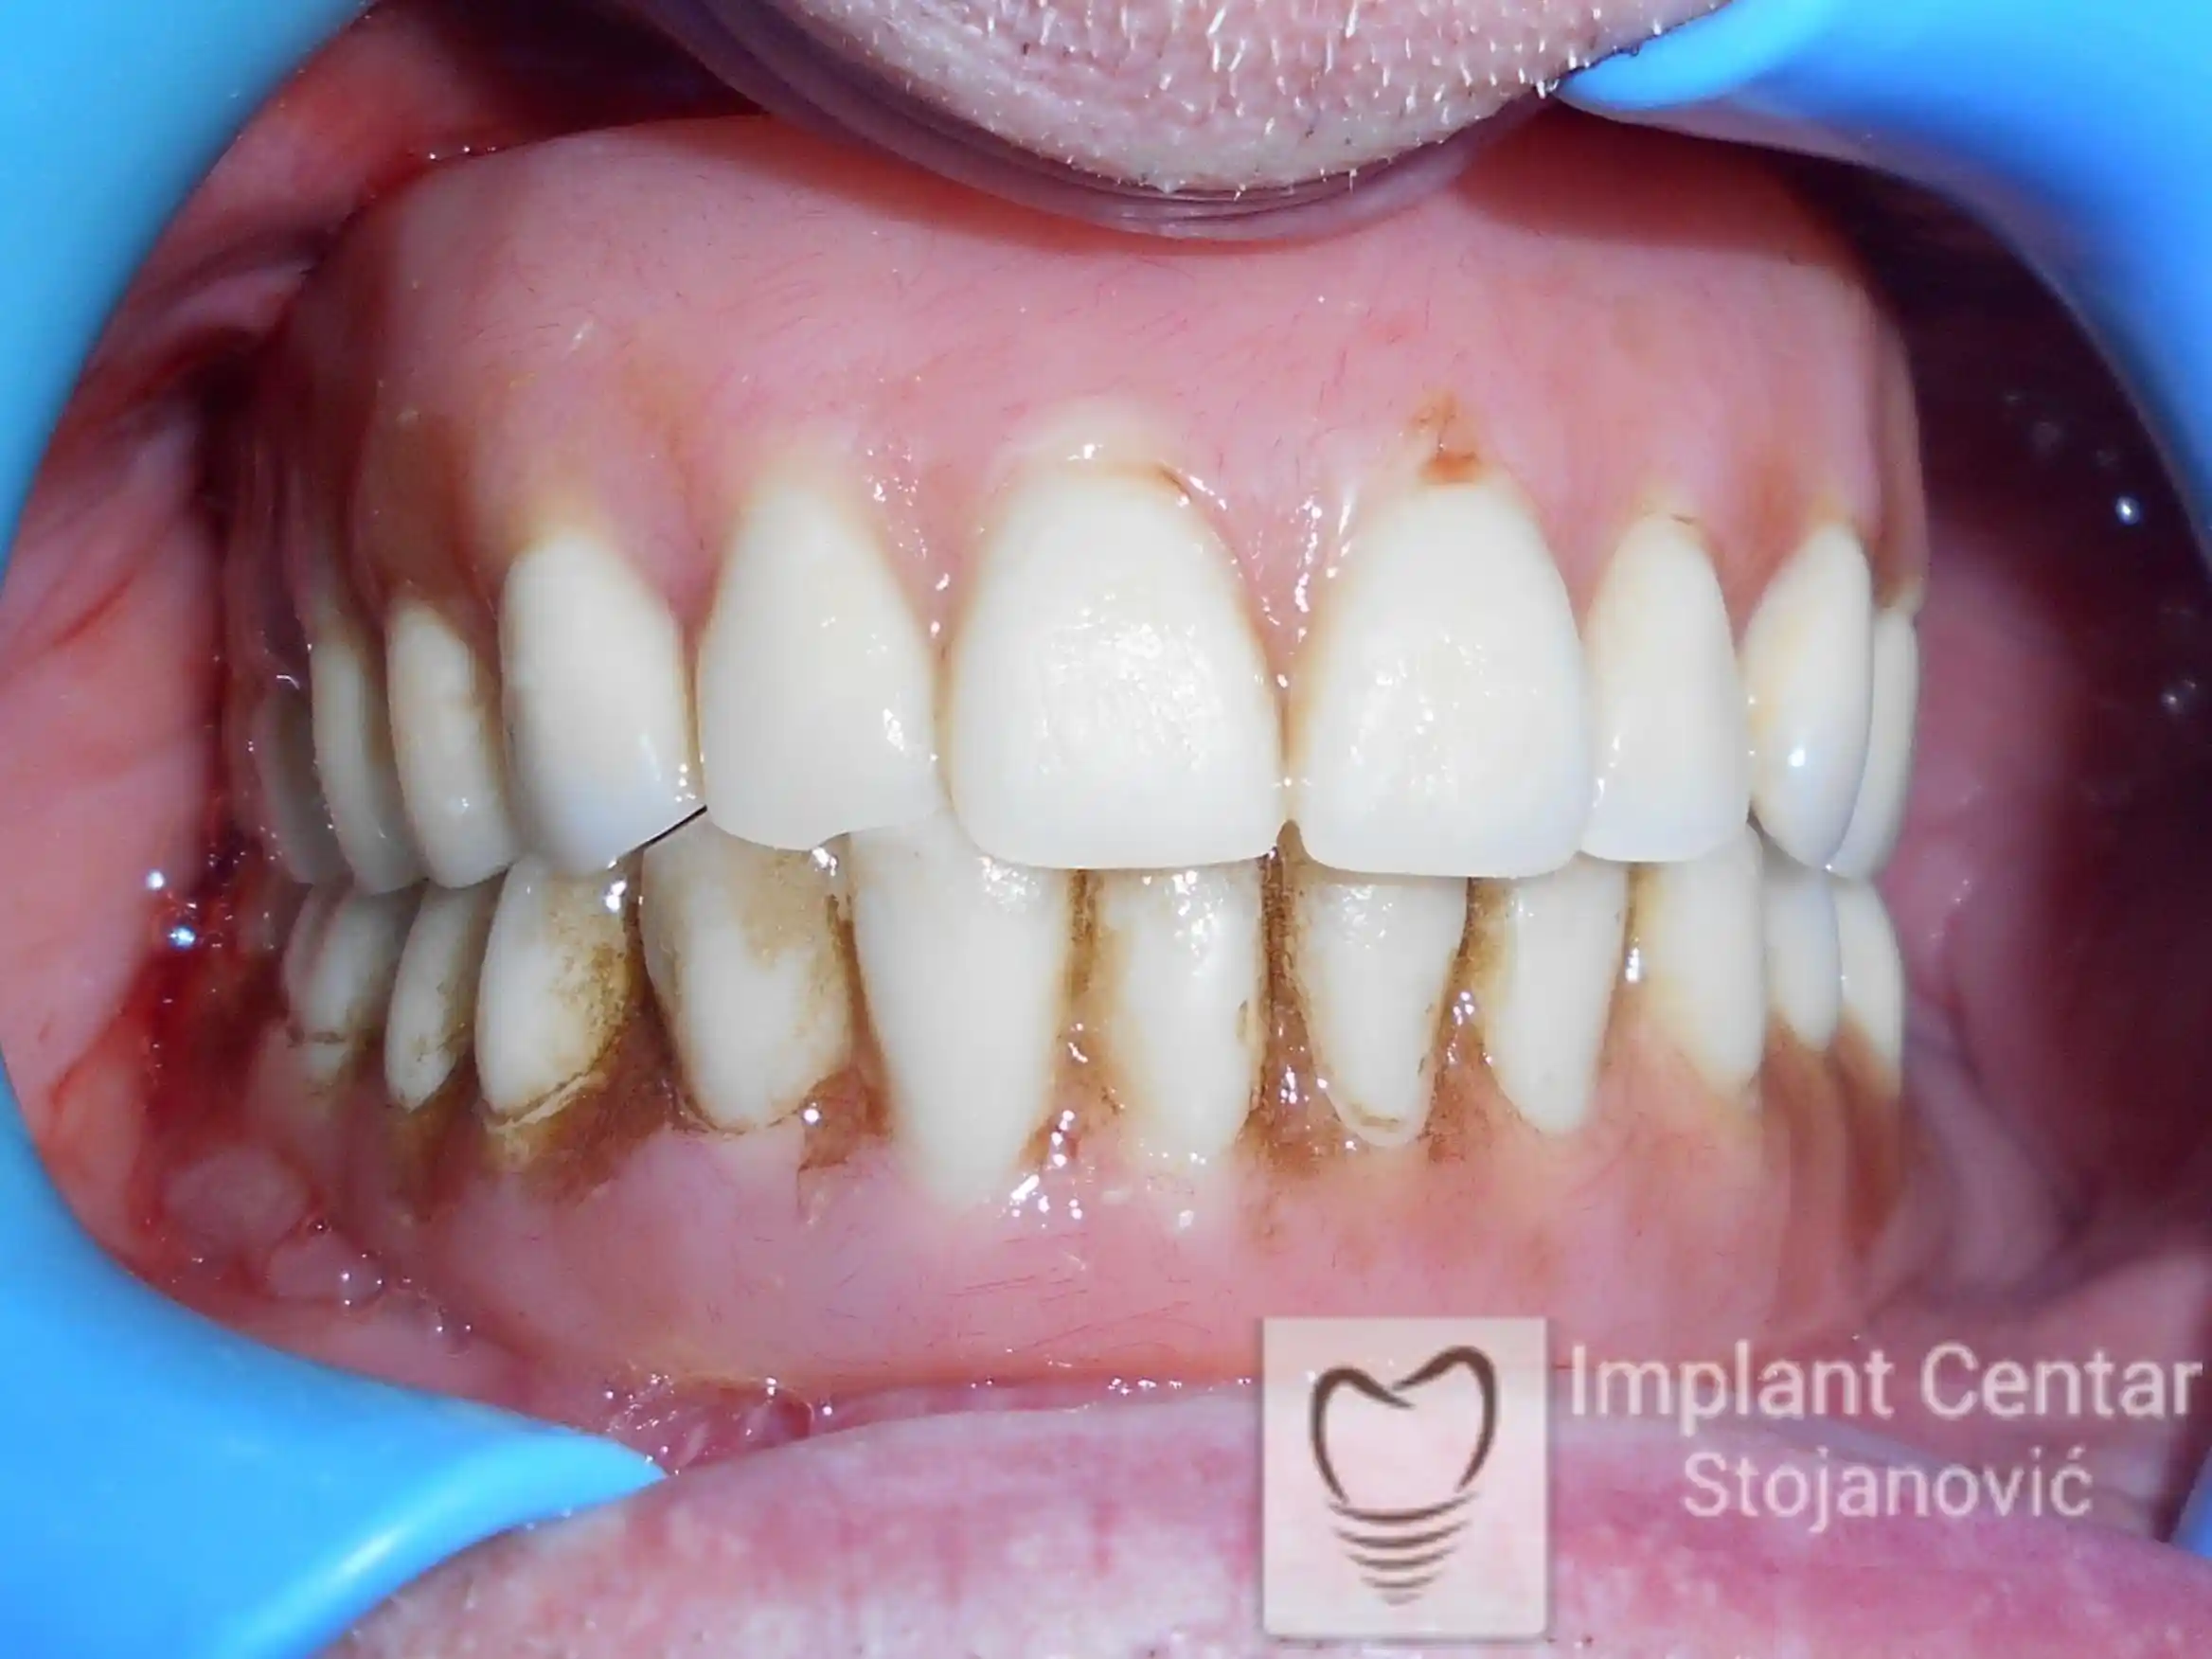

Nakon ugradnje implantata i pripreme preostalih zuba, pacijentu su izrađene fiksne privremene krunice, čime je postignut eugnatan zagriz već nakon jednog dana (slika 8, 9 i 10). Tokom perioda osteointegracije, pacijent se postepeno privikavao na novi položaj vilica i zagriz.

Po završetku perioda integracije, izrađeni su definitivni cirkonijum-keramički mostovi, čime je postignuta potpuna rekonstrukcija zagriza, kao i značajno poboljšanje estetike i oralne funkcije (slika 12, 13, 14 i 15).

Na slikama 5. i 6. prikazan je izgled definitivnih cirkonijum-keramičkih mostova na implantatima.

Tokom perioda osteointegracije, pacijent je bio zbrinut fiksnim privremenim krunicama na implantatima, čime su očuvani estetika i funkcija. Nakon završetka perioda integracije, izrađeni su definitivni cirkonijum-keramički mostovi (slika 6 i 7 ).